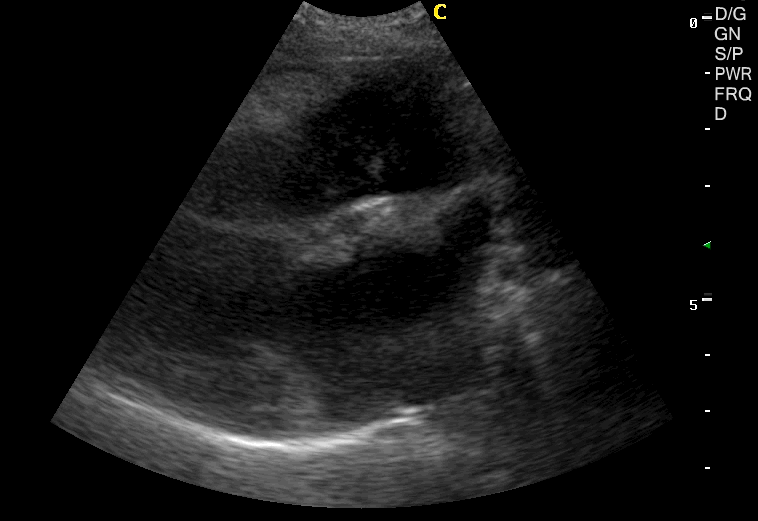

Ασθενής: 11 ετών , θηλυκό στειρωμένο Beagle.

Ιστορικό: Συστήθηκε υπέρηχος λόγω περιοδικού βήχα, ήπιας κόπωσης στη βόλτα και βυθιότητα στην ακρόαση της καρδιάς.

Ευρήματα:

- Ευμεγέθης μάζα η οποία ξεκινούσε από την βάση της καρδιάς ανάμεσα από τα δύο μεγάλα αγγεία (πνευμονική αρτηρία και αορτή) και εκτεινόταν προς τον δεξιό κόλπο. Η μάζα ήταν μικτής ηχογένειας με αυξημένη αγγείωση και περιόριζε την κοιλότητα του δεξιού κόλπου.

- Παρουσία μικρής περικαρδιακής συλλογής με λεπτοκοκκώδες υγρό.

- Στοιχεία ενδοκάρδωσης της μιτροειδούς βαλβίδας, με όγκο αναγωγής προς τον αριστερό κόλπο ( 1.5m/s).

- Ήπια διάταση των ηπατικών φλεβών και της οπίσθιας κοίλης φλέβας.

Διάγνωση: Λόγω της θέσης της μάζας η ιδιοκτήτρια δεν θέλησε περεταίρω διερεύνηση και επιλέχτηκε υποστηρικτική θεραπεία. Με την μεγαλύτερη συχνότητα εμφάνισης από όλες τις νεοπλασίες της καρδιάς, αναφέρεται στη πρόσφατη βιβλιογραφία το αιμαγγεισάρκωμα (40%)και ακολουθεί το χημειοδέκτομα (17.3%)2. Η εμφάνιση μεταστατικών αλλοιώσεων στην καρδιά είναι σπάνια1-2 αλλά την μεγαλύτερη σε συχνότητα εμφάνιση έχει το λέμφωμα2.